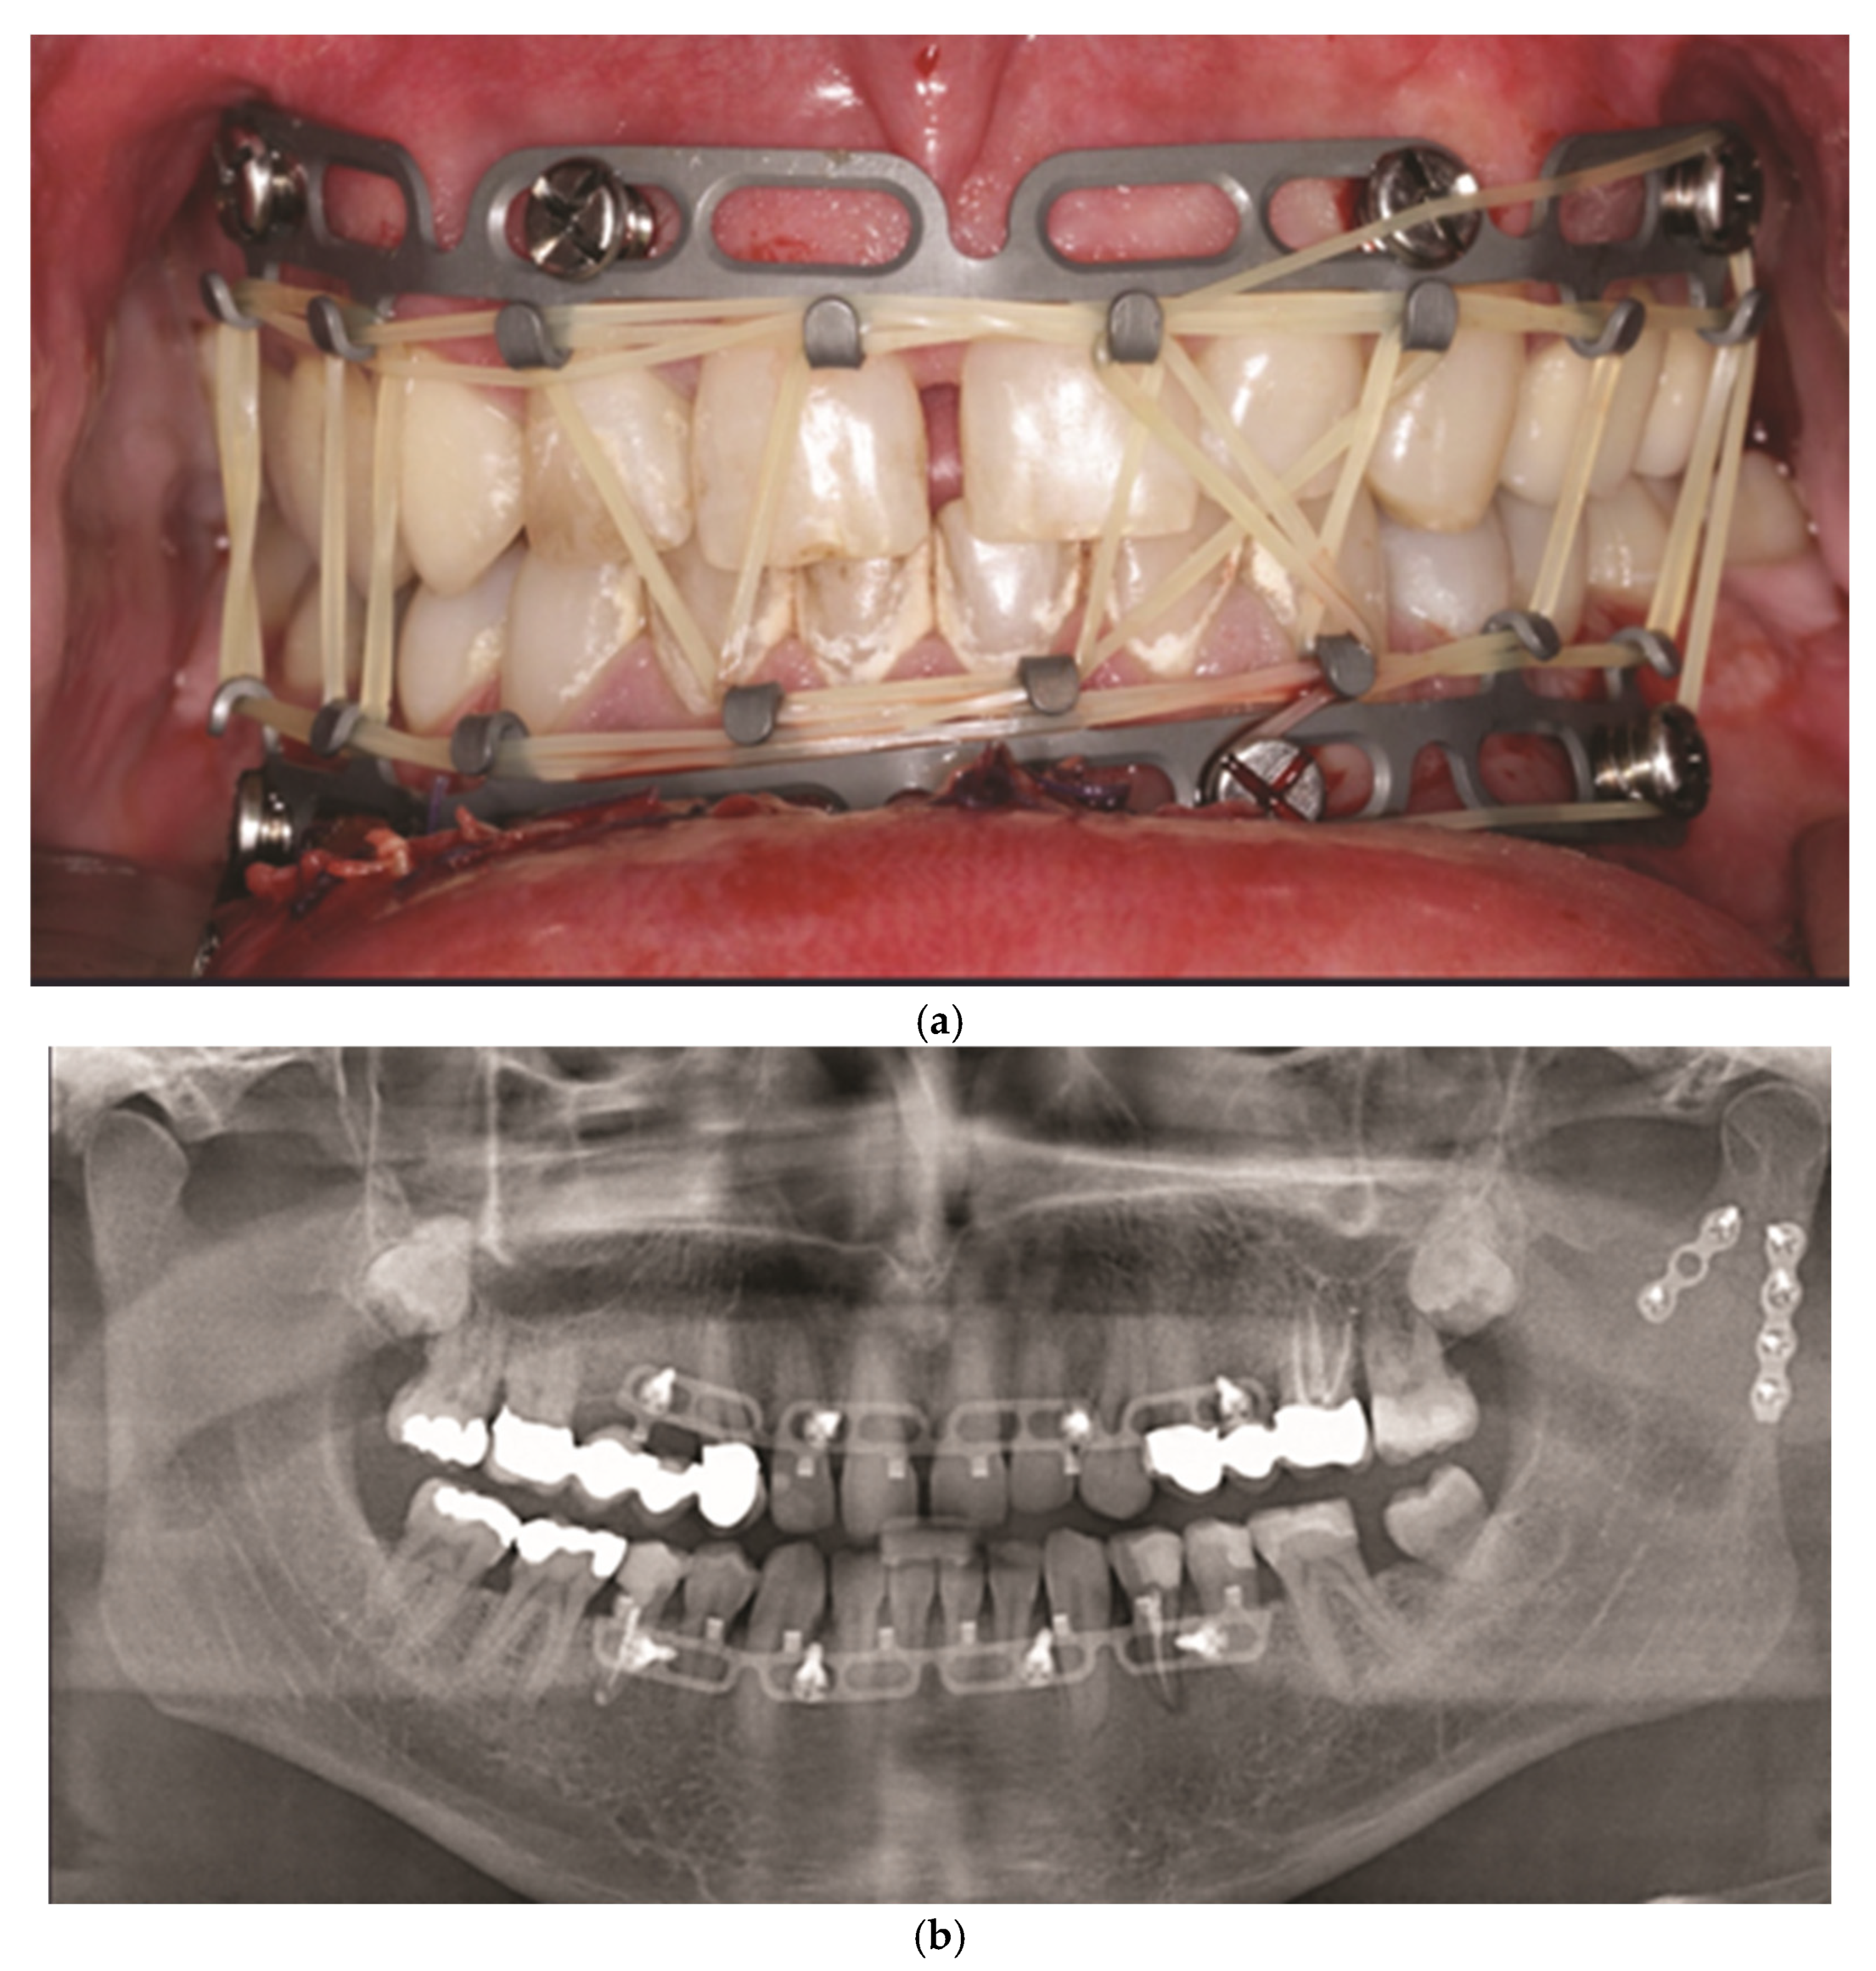

3.11. MatrixWave MMF System (DePuySynthes) - Clinical Study

3.12. Juxtaposition of the League of Commercial Hybrid MMF Systems